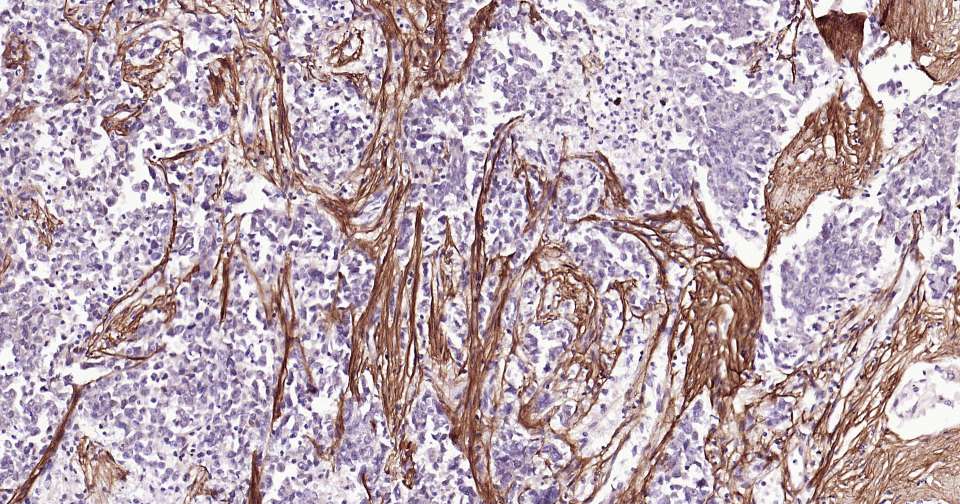

Immunohistochemical analysis of paraffin embedded human stomach tissue slide using IHC0356H (Human Periostin Kit).

Immunohistochemical analysis of paraffin embedded human mammary gland tissue slide using IHC0356H (Human Periostin Kit).

Immunohistochemical analysis of paraffin embedded human colon tissue slide using IHC0356H (Human Periostin Kit).

Immunohistochemical analysis of paraffin embedded human lung cancer tissue slide using IHC0356H (Human Periostin Kit).